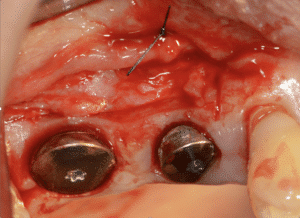

Fig.1 : Patient 1 : Absence de tissu kératinisé en quantité suffisante en vestibulaire

des implants et 15 et 16 après 3 mois d’ostéointégration.

Fig.2 : Préparation du lit receveur.